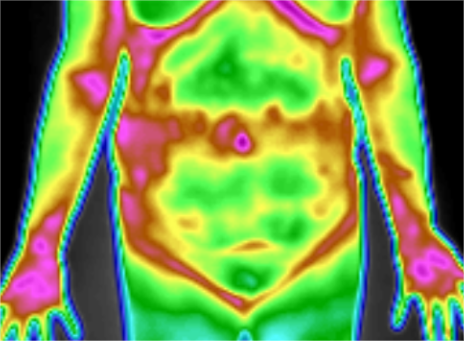

今年10月份,湖南杨女士到常德市第一人民医院健康管理中心体检。在了解到中心有一项GTT全维度热成像扫描,能够快速筛查全身疾病后,杨女士当即决定加项GTT扫描。

扫描完成后,热成像评估专家发现杨女士的结肠区功能代谢热值及热形态分布高度异常于正常人群,经联合会诊,考虑其存在较高的肠道疾病风险,遂建议其加做肠镜检查或是及时到专科就诊。

此次,杨女士所做的GTT全维度热成像扫描是利用高精度传感器被动接收人体远红外热辐射,根据其病变部位与周边相对正常组织代谢热分布的差别,实时判断病变组织的代谢状态,再综合GTT大数据库风险评估等级,对疾病做出早期风险评估,可帮助体检者实现全身疾病的早筛早查。

GTT扫描过程无创、无痛、无辐射,通过GTT扫描首先筛查出肠癌高危人群,再结合肠镜检查进行精准诊断,为无症状人群的肠癌早筛提供了一个有效可行的路径。